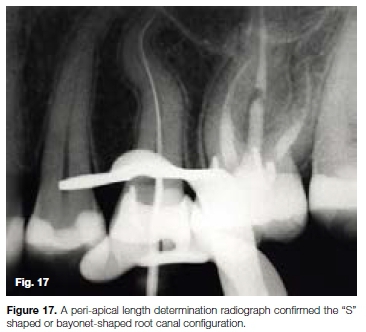

The patient, a 37 year old female presented with irreversible pulpitis on her maxillary left first second premolar. The tooth had been previously restored with a large composite resin restoration and two retention pins. A preoperative peri-apical radiograph (Figure 16) and a length determination radiograph (Figure 17) revealed and confirmed a challenging "S" shaped or bayonet-shaped root canal configuration.